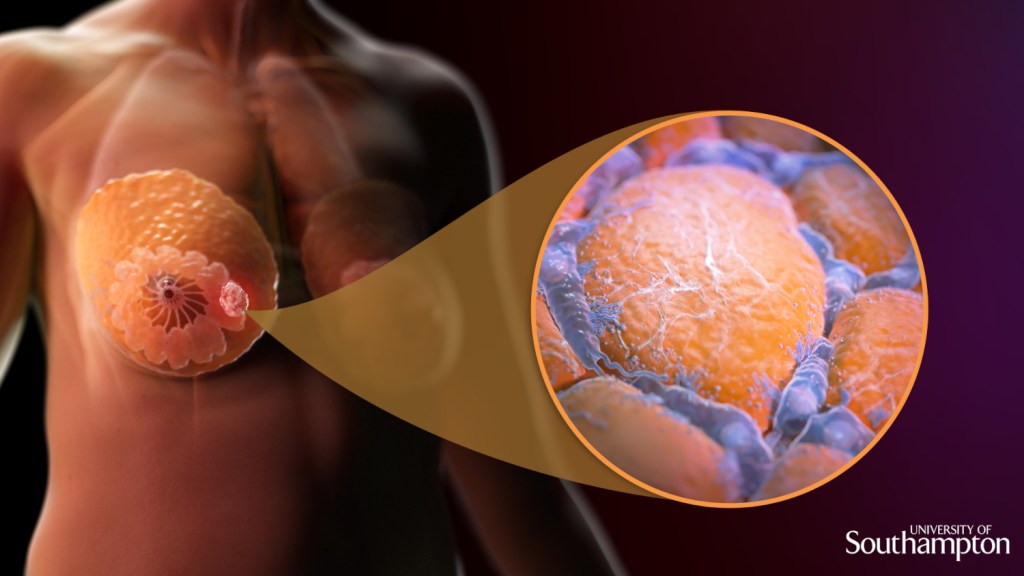

Le cancer du sein est une maladie qui touche principalement les femmes, mais qui peut également toucher les hommes. Il s’agit d’une tumeur maligne qui se développe dans les cellules du sein.

Comment se manifeste le cancer ?

Les signes et symptômes du cancer du sein peuvent varier d’une personne à l’autre. Dans certains cas, la maladie peut être asymptomatique, c’est-à-dire qu’elle ne présente aucun symptôme. Dans d’autres cas, les signes les plus courants comprennent une augmentation de la taille du sein, une douleur ou une sensibilité accrue, une bosse ou une masse dans le sein, des changements dans la forme ou la texture du sein, des écoulements de liquide mamelonnaire et des changements de couleur ou de texture de la peau du sein. Toutefois, le risque de développer un cancer du sein au cours de la vie d’une femme est d’environ 1 sur 8. Il est plus fréquent chez les femmes âgées de 50 ans et plus. Les facteurs de risque pour le cancer du sein comprennent également une prédisposition génétique, l’âge, les antécédents familiaux de cancer du sein, l’utilisation prolongée de contraceptifs hormonaux, une première menstruation précoce, une ménopause tardive, une grossesse tardive ou l’absence de grossesse, la consommation d’alcool, l’obésité et le manque d’activité physique. Par ailleurs, le dépistage précoce peut aider à améliorer les chances de survie. Les mammographies sont recommandées pour les femmes âgées de 50 à 74 ans tous les deux ans. Les femmes à risque élevé peuvent nécessiter un dépistage plus fréquent ou une surveillance supplémentaire.